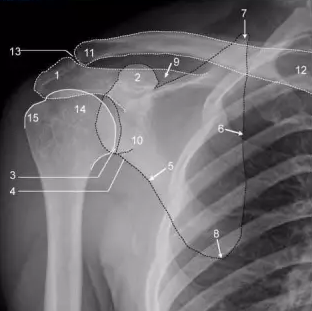

拍了平片(图1)。这表明所有部件对齐良好,关节内没有衬垫断裂或碎片的迹象。他放心了,他的症状得到了保守的治疗。三个月后,他的症状有所恶化,但经进一步评估,临床表现或X光片没有变化。此时对衬垫骨折或腰肌腱炎进行了鉴别诊断。